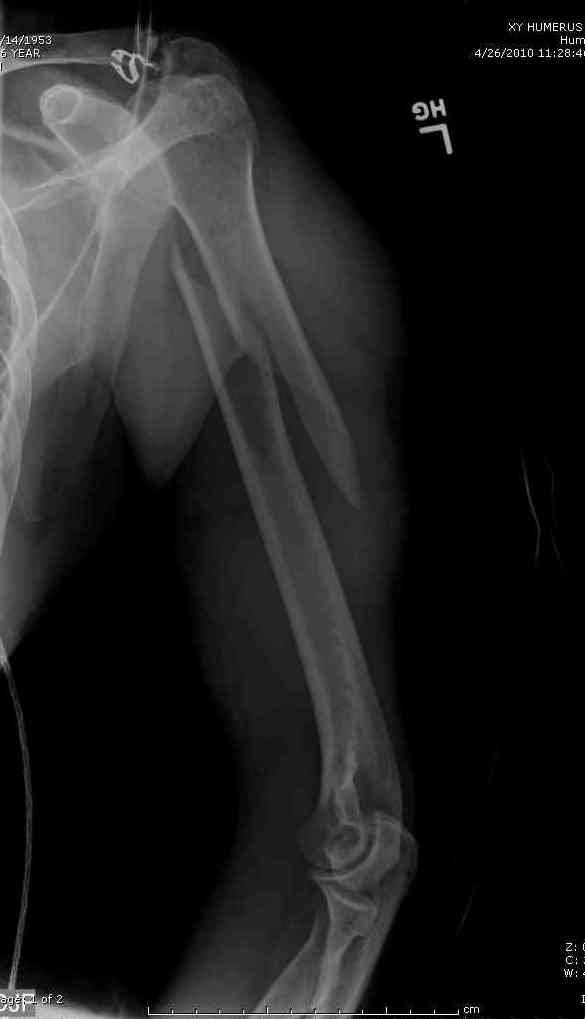

Кроме интрамедуллярного остеосинтеза, имеются другие варианты фиксации, наружный фиксатор и например здесь перелом плеча с повреждением нерва леченный открытым методом. Применен задний доступ с инспекцией нерва, межфрагментарная компрессия, фиксация узкой пластиной 4.5 мм.